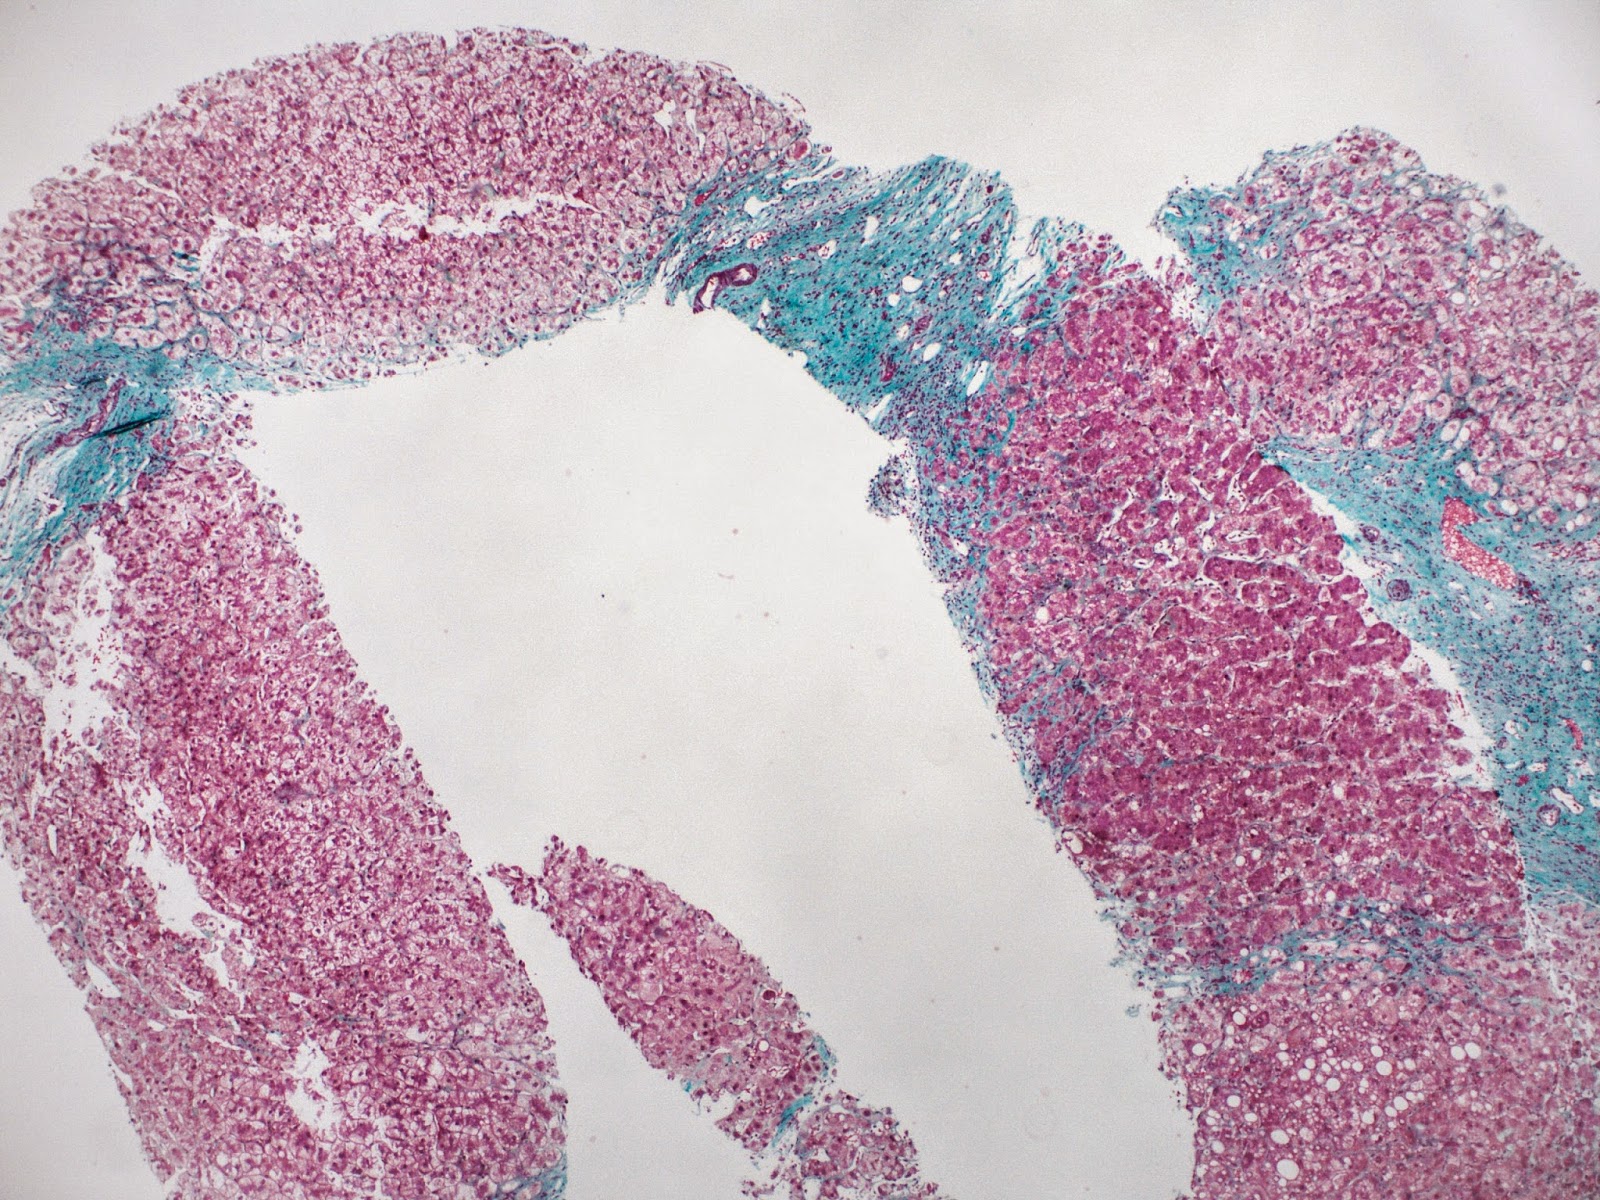

Figures 5 and 6 show portal-portal bridging fibrosis at least.